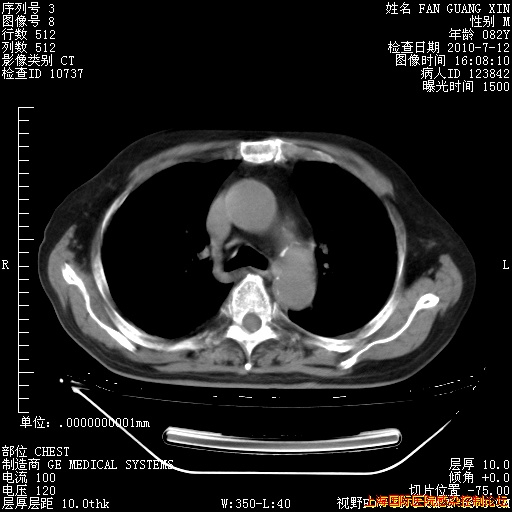

补发6月12日肺部CT肺窗

6月12日肺窗

6月12日纵膈窗

今天复查CT

今天CT

整整相隔30天的肺部CT好像有所好转啊。甲强龙减量第3天,需要观察体温。

海管,自昨日你和我通完话后,不知您岳父消化道症状有无缓解?体温怎样?阅读7.12日胸部ct,个人认为目前激素治疗是有效的,甲强龙减量是适宜的。因在抗痨治疗,需密切观察肝功、肾功能和血常规。不过,老年、长期住院和大量使用激素,很担心菌群失调发生